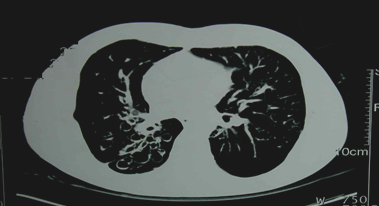

②胸部CT

可显示管壁增厚的柱状扩张或成串成簇的囊状改变。高分辨CT(HRCT)(可确诊)。